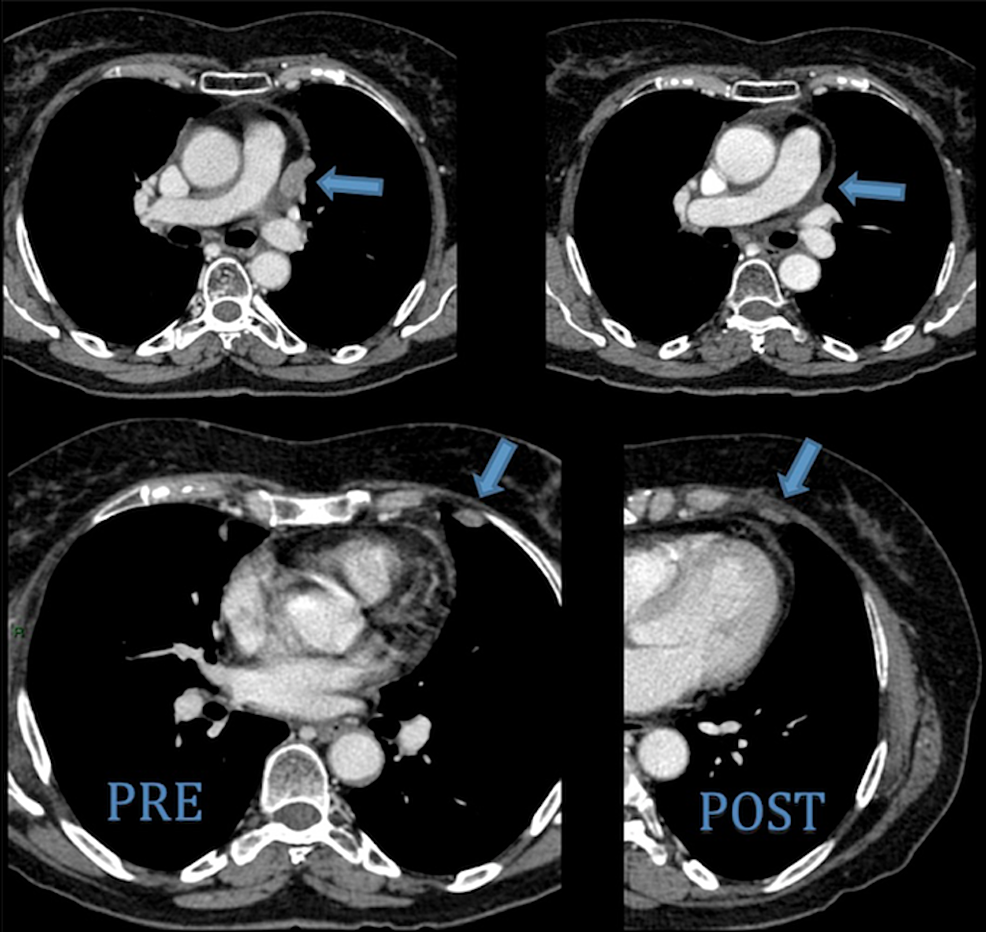

Cureus A Rare Case of a HighGrade Thymic Squamous Cell Carcinoma Presenting as Cardiac Tamponade Thymic Carcinoma Survivors Learn about thymoma and thymic carcinoma signs, diagnosis, causes, risk factors, and treatment options. Patients, family members and carers share their stories of how thymic cancer has affected them, as well as. Survival rates are grouped based on how far the cancer has spread, but your age, overall health, type of thymus cancer, whether the entire. The recovery from treatment. Thymic Carcinoma Survivors.